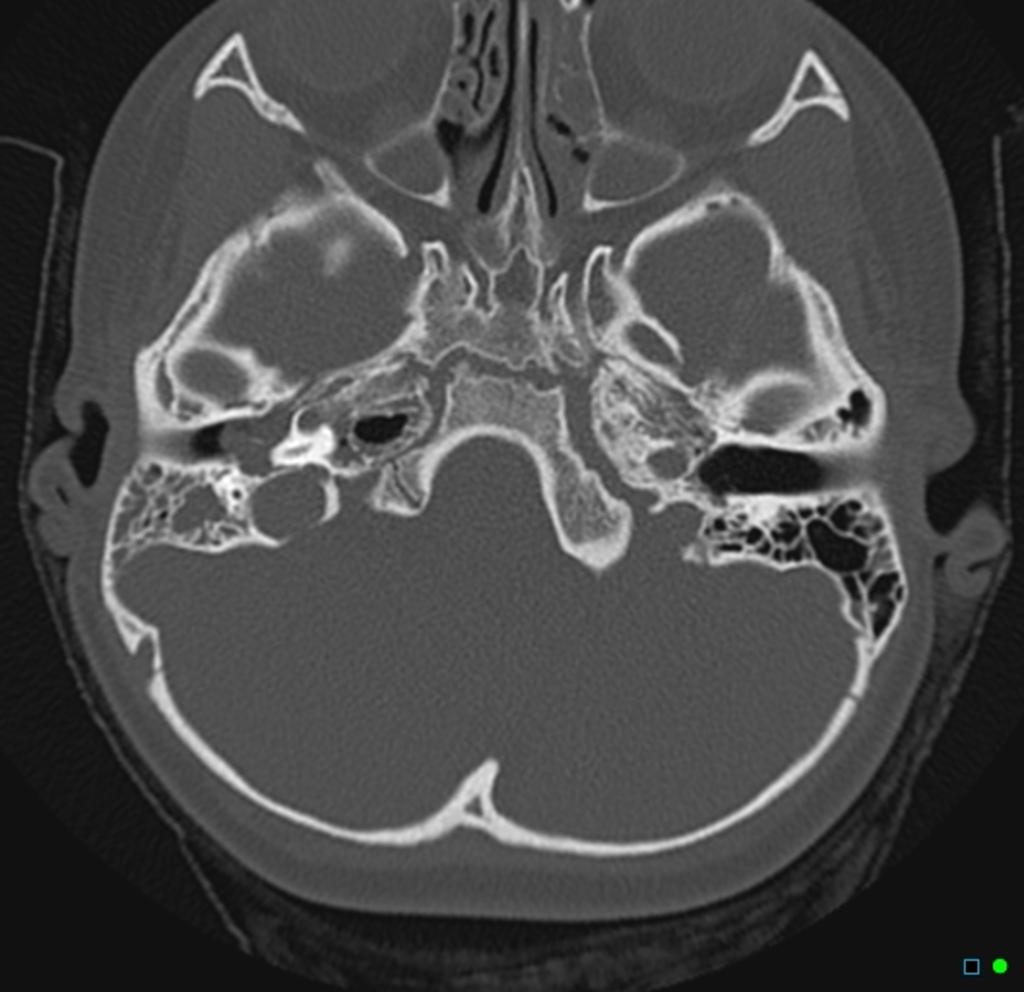

Исследование антрума: важные моменты